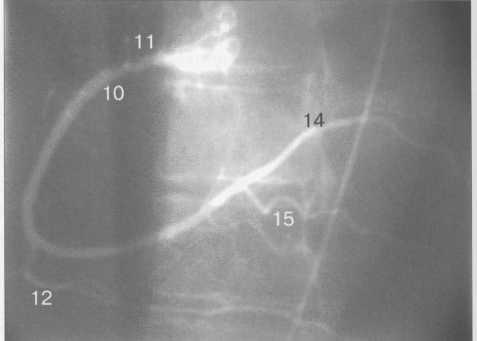

Анатомия коронарных артерий: КТ-изображения